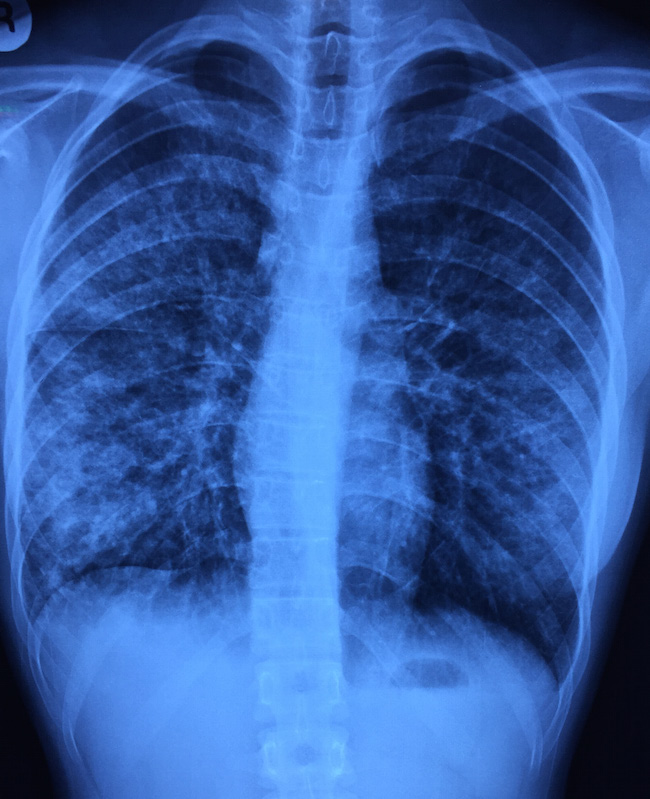

On clinical examination, there were coarse crackles over the right lower lung field. Her oxygen saturation was 95% on room air. Her blood pressure was 91/54 mmHg. There were no cardiac murmurs audible nor a rash. Her white cell count as elevated (14K), with predominantly neutrophils. Renal function was normal and the chest X-ray is shown below.

The chest X-ray shows bilateral infiltrates, far more prominent on the right where the abnormal breath sounds were heard. The appearance is not that of a dense lobar consolidation that is more associated with pneumococcal pneumonia. Some posters on Facebook have suggested Pneumocystis jiroveci pneumonia (PCP or PJP) if the setting is right. She did have one sexual partner, but only for one year (having said which, such history is often unreliable), and the progression is much too fast for PCP in a patient with HIV.

A HIV test was performed nonetheless (negative), and she was started on antibiotics as for community-associated pneumonia (ceftriaxone and clarithromycin, given the appearance of the X-ray). However, all bacterial cultures from blood and sputum were negative, and a throat swab came back positive for influenza A. Multiple studies, including this recent one from NEJM, have shown that respiratory viruses as a group are the most common cause of community-associated pneumonia, even those requiring hospital admission. It is important to consider this possibility and order the appropriate tests (which unfortunately are more expensive than a course of subsidised antibiotics in our public sector hospital setting!) in order not to over-treat the patients with more broad-spectrum antibiotics when symptoms fail to resolve with initial antibiotics.